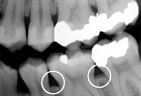

Periodontitis

Advanced Periodontitis